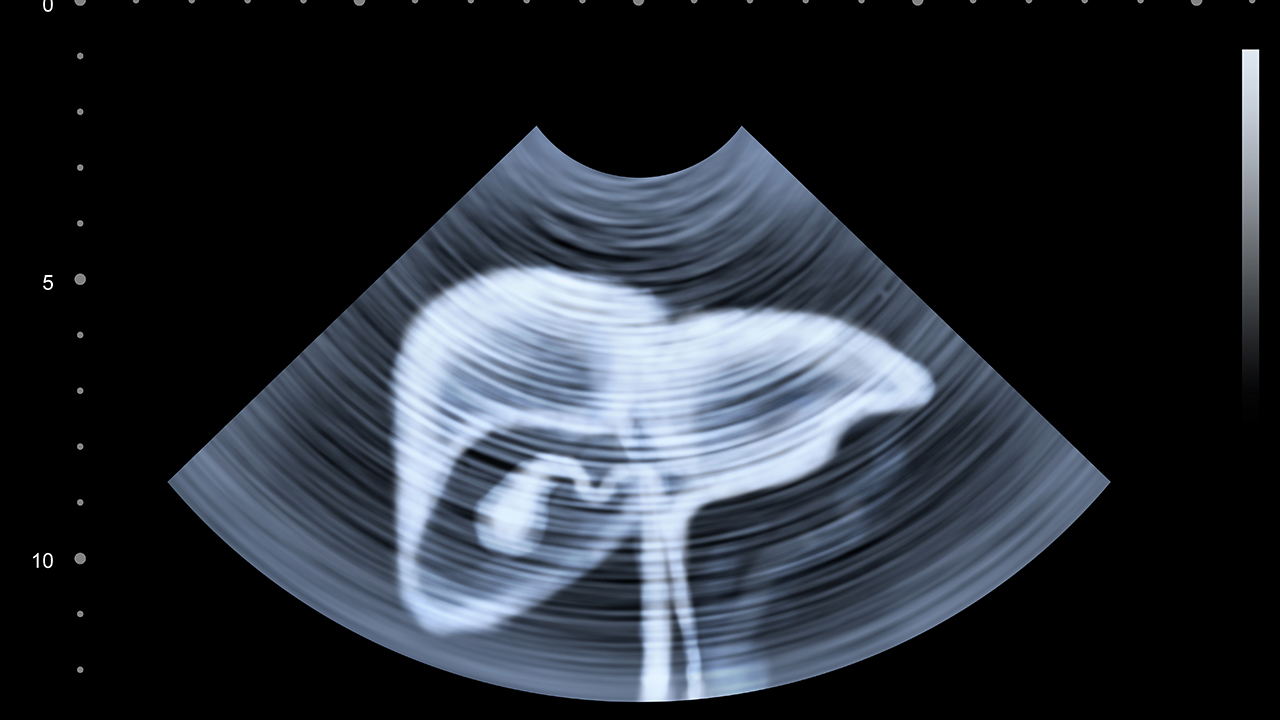

肝癌是一种常见的恶性肿瘤,其发病原因复杂,包括慢性肝炎病毒感染、长期酗酒、肝硬化等。早期诊断和规范治疗对提高患者生存率至关重要。